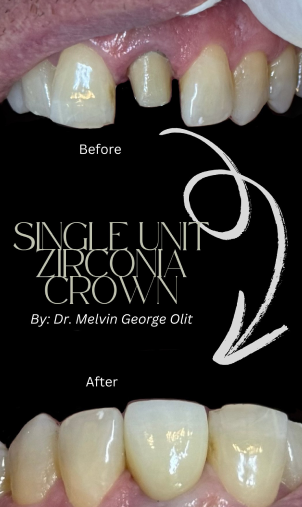

Single Unit Zirconia Crown

The single unit zirconia crown procedure restores damaged or weakened teeth with a strong, natural-looking cap made from zirconia—a durable, biocompatible material known for its strength and lifelike appearance. It’s an ideal choice for long-lasting protection and aesthetics.

The process starts with reshaping the tooth and taking precise digital or physical impressions. A custom crown is then fabricated to perfectly match your bite and surrounding teeth. Once ready, it’s securely bonded to restore full function and appearance.

Zirconia crowns not only enhance your smile but also provide excellent durability against wear, making them a great option for both front and back teeth.

Looking to restore your tooth’s strength and beauty? Schedule your visit today and discover the benefits of zirconia crowns.

Single Unit Zirconia Crown